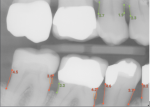

Since 2020, technological advancements have resulted in an exponential increase in the utilization of artificial intelligence in daily life, particularly in the field of dentistry. Leading dental clinicians are working with machine-learning scientists to develop and encode computer algorithms to measure and analyze radiographs, photographs, clinical assessments, and chart notes with dentist-level accuracy and understanding. This capability will result in a highly accurate output and clinically relevant results. Leading companies have developed algorithms to detect caries and periodontal disease, in addition to a wide array of clinical determinants. These algorithms and AI-enhanced software can help hygienists improve patient communication and demonstrate the necessity for treatment. The algorithms are built on millions of data points learned through rigorous clinical inputs, and are currently achieving equal to, and in some instances better than, single clinician accuracy.